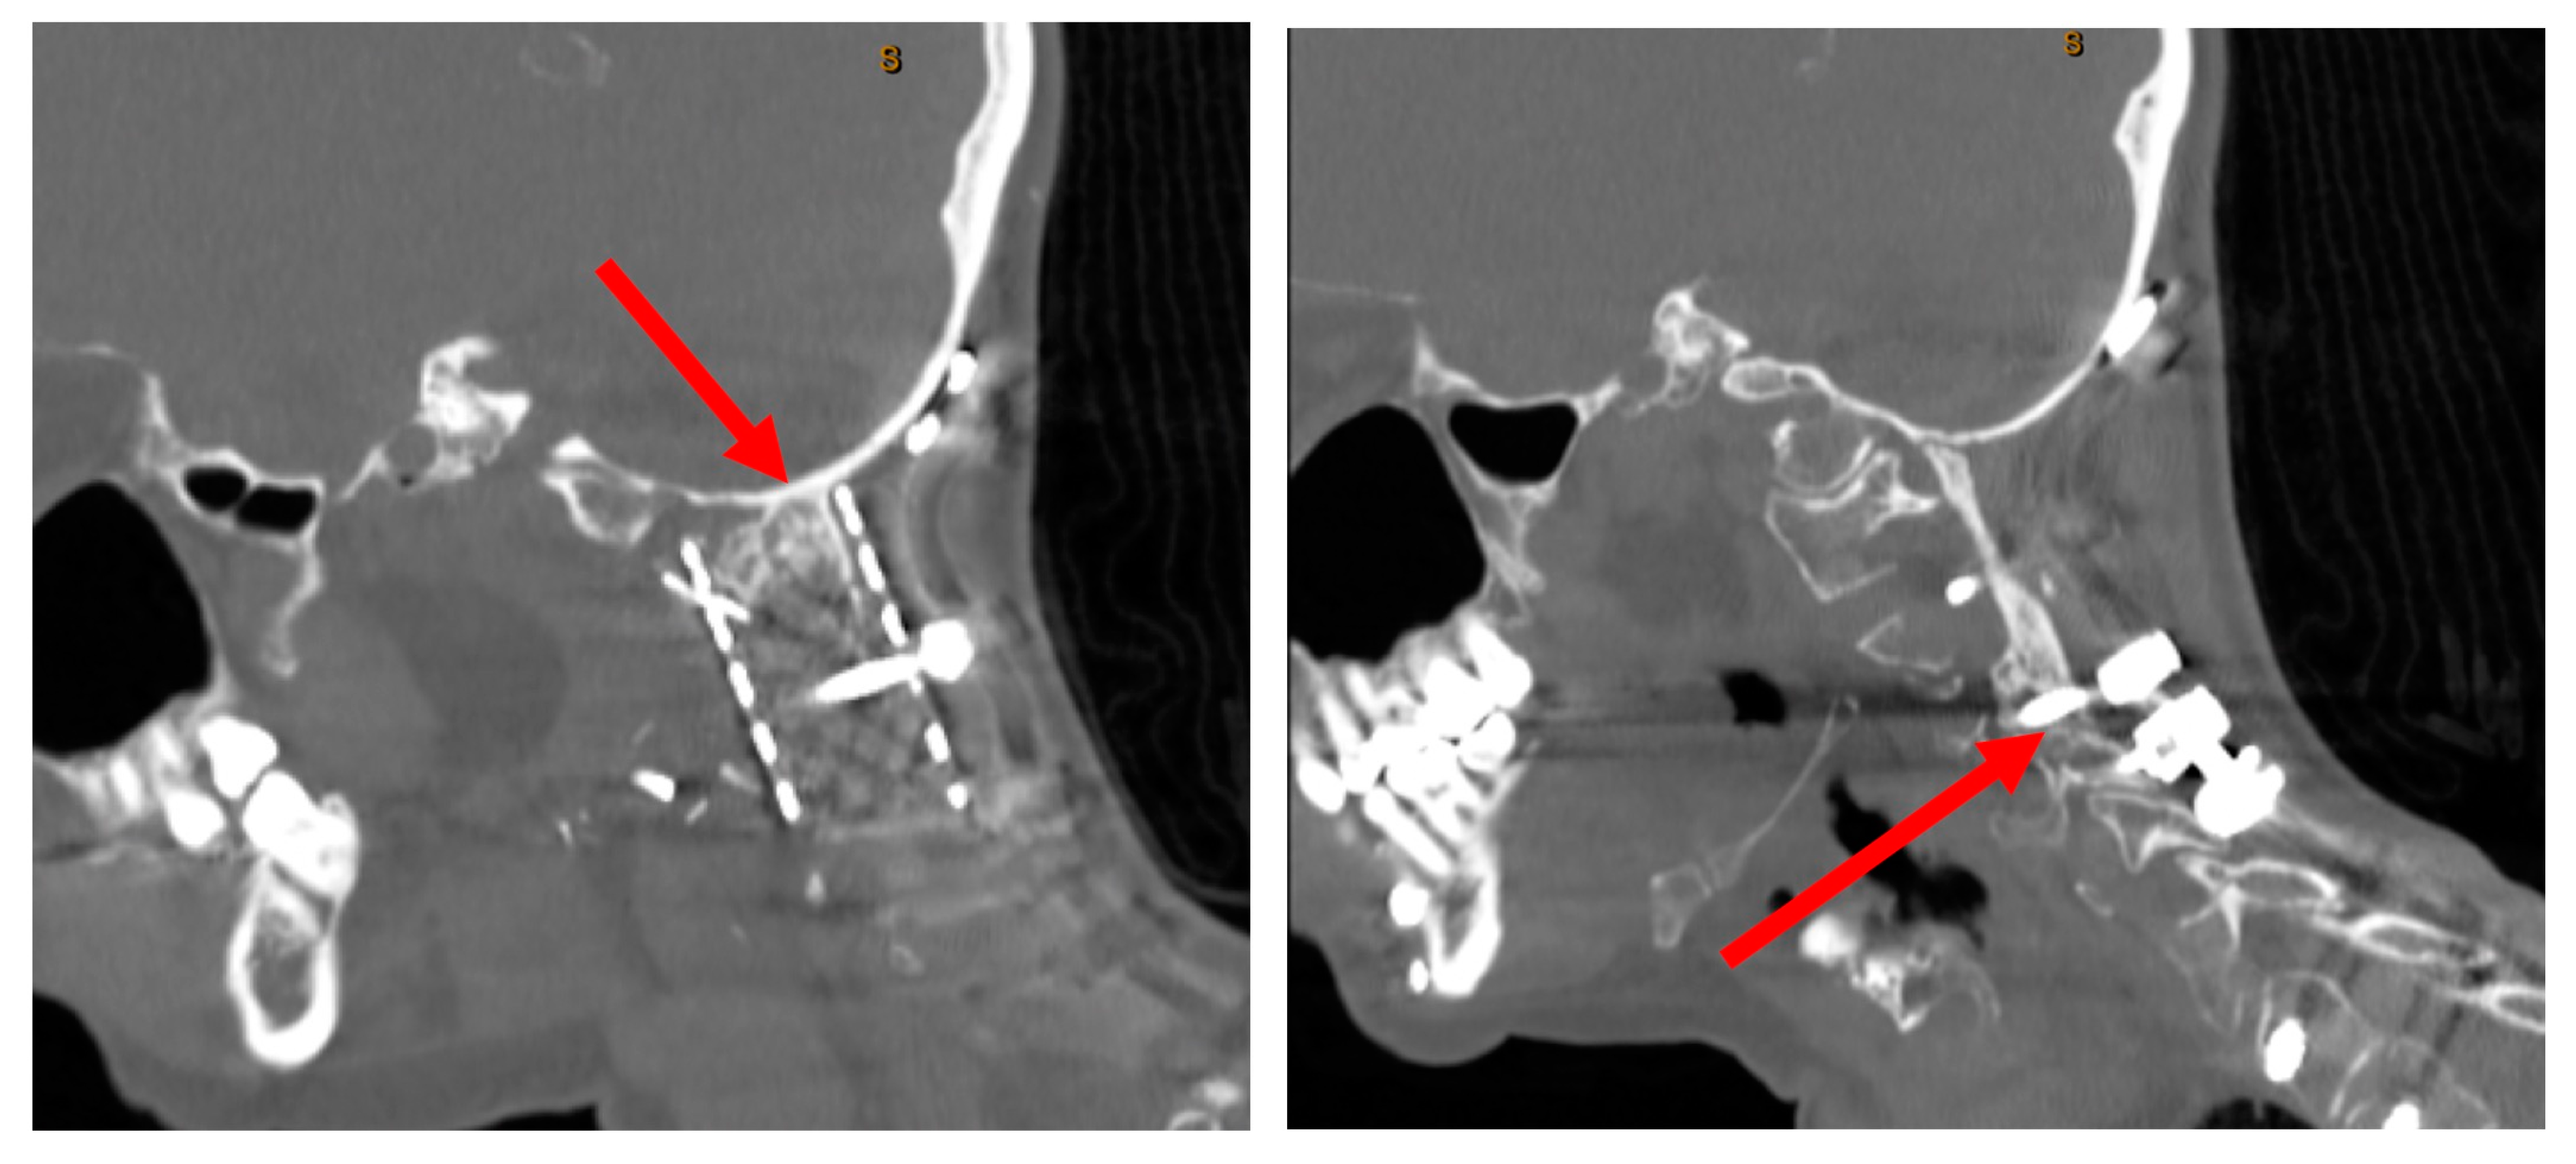

3.2.2. Imaging and Classification

3.2.3. Treatment

3.2.4. Outcomes